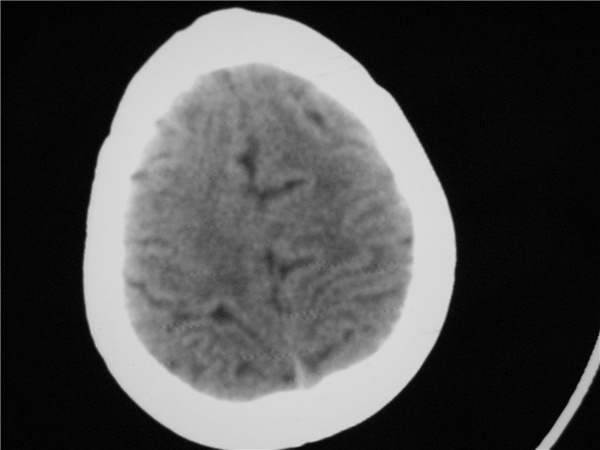

标题: PED2843: CT-23675 F 4Y 大家看看颅内有问题没。 [打印本页]

标题: PED2843: CT-23675 F 4Y 大家看看颅内有问题没。

未见明显异常。

四脑室扩大,三脑室稍扩大上移

胼胝体发育不全??

颅脑ct平扫未见异常。

颅脑ct轴位平扫颅内未见明确异常。

四脑室扩大,密度降低,图像的问题?建议mr扫描。